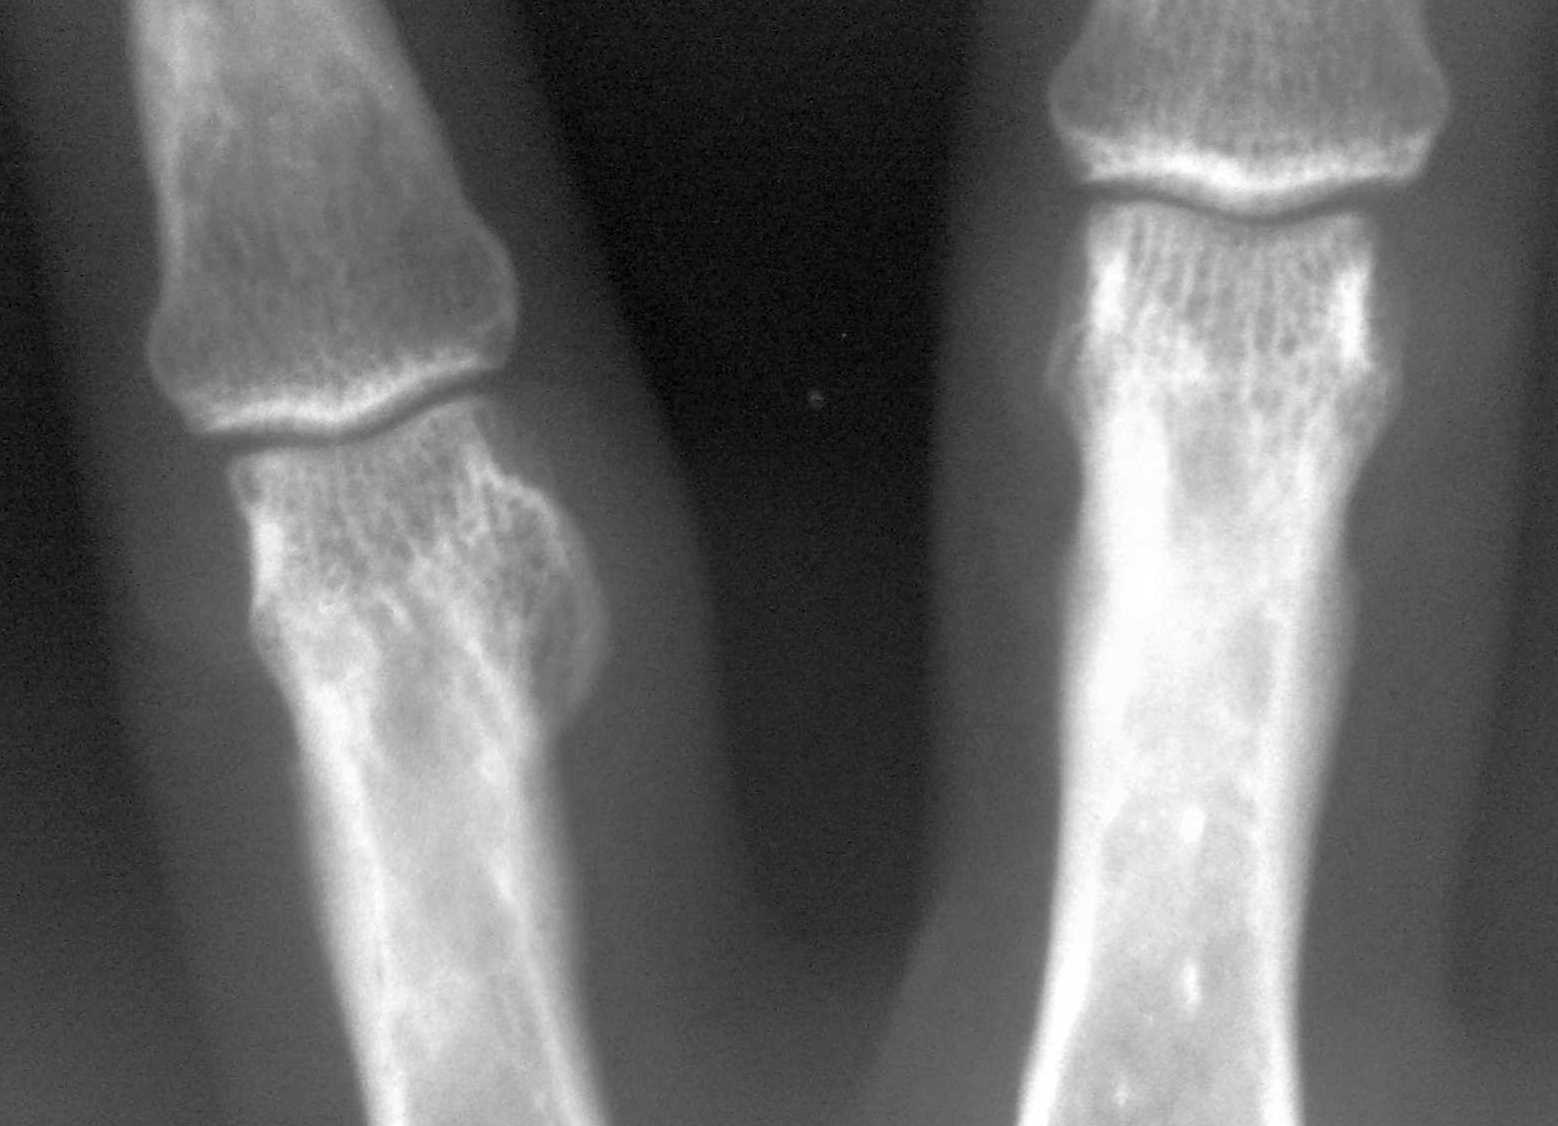

- Рентгенография. Исследование проводится в двух проекциях, что позволяет точно определить локализацию и размеры остеомы, а также степень разрушения окружающих тканей. Однако небольшая опухоль может быть не видна на рентгеновском снимке, поэтому этот метод не отличается высокой точностью.